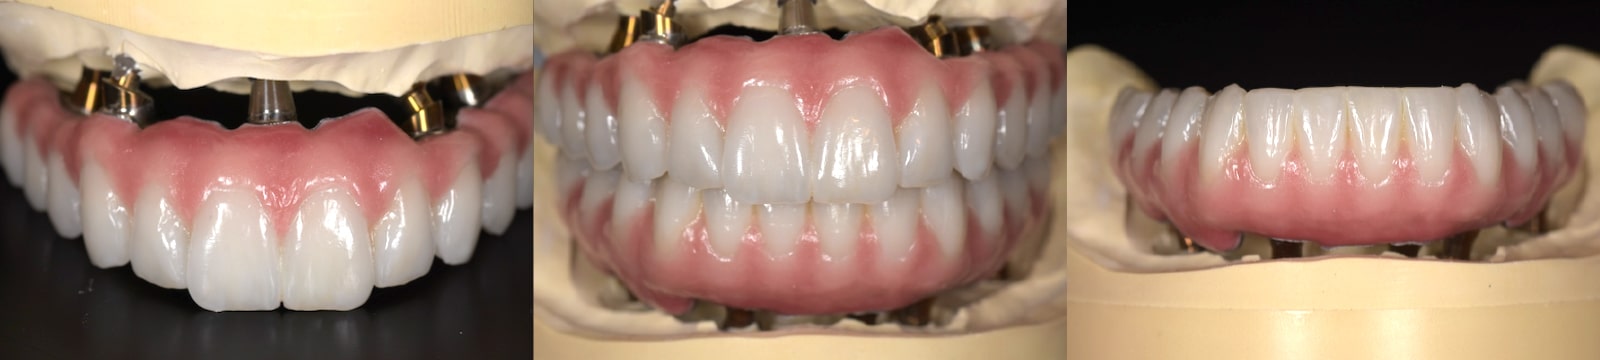

とびきり美しい上部構造

ただ治すのではなく、美しく治す。しかも、とびっきり美しく治すことにこだわっています。そのため、数々の賞を受賞する腕の良い歯科技工士と連携して歯をデザインしています。